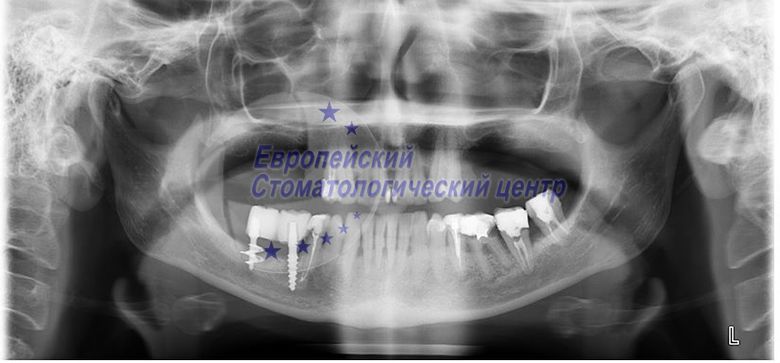

OPG before surgery